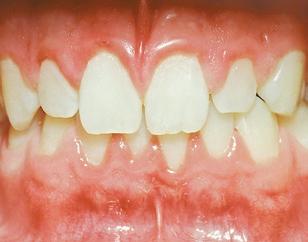

THE PERIO-ORTHO SYSTEMIC LINK

The perio-ortho systemic link has been clearly connected through the years.

As

healthcare providers, we should focus on both disease prevention and treatment modalities when dealing with periodontal disease.

It is now clear that orthodontic health is vital for periodontal and systemic health. Therefore, orthodontic treatment should be one of the treatment options considered in prevention plans, as well as restorative plans in dentistry. Evidence based dentistry has shown that more than just three millimeters of crowding can be a host factor for periodontal disease. Therefore, preventative treatment to avoid periodontal issues should consist of placing the teeth in proper alignment, including reduction or elimination of crowding. Research has also shown that there is significantly greater plaque accumulation in crowded areas. Interestingly, research also indicates that the bacteria present in crowded areas consistently represents more species of periodontopathogens than bacteria from non-crowded regions. The pathogens are more virulent in the areas that are more crowded because they become anaerobic, meaning they grow in the absence of oxygen. As plaque accumulation increases subgingivally, or beneath the gums, the amount of periodontopathogens increases. 2

If we can reduce crowding, then we can reduce aggressive periodontal pathogenic bacteria, which can subsequently decrease the risk of periodontal disease as well as the inflammatory disease processes in the rest of the body. Our currently preferred options for reducing crowding include traditional braces and clear aligner therapy, such as Invisalign®